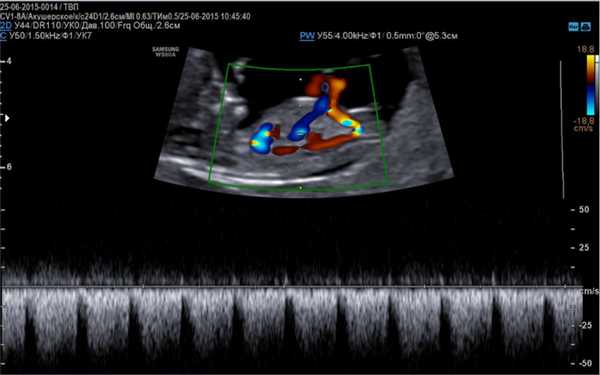

Эхо-КГ (эхокардиография) плода

Эхо кг плода является современным методом диагностики сердечно-сосудистой системы. Суть метода заключается в определении возможных патологических изменений в формировании сердца плода, которые визуализируются при помощи высокочастотных волн. Процедуру проводят по показаниям, в тех случаях, когда во время прохождения плановой УЗИ диагностики у беременной было выявлено отклонения от нормы. Какие ещё существуют показания к проведению исследования, и как оно осуществляется?

Эхокардиография плода - это не инвазивный метод исследования, способный визуализировать сердце и сосуды в период внутриутробного развития ребенка при помощи ультразвуковых волн. Современные технологии позволяют применять в пренатальной диагностике высокоточные и безопасные аппараты, которые гарантируют безопасность при проведении данного исследования.

Основой для качественной диагностики является наличие программы, позволяющей определить функциональное состояние сердечно-сосудистой системы на приборе, оснащенным специальным датчиком, имеющим частоту сканирования не менее 5 МГц, а также цветное картирование системы кровообращения и доплер.

- Доплер эхокардиография, более расширенная методика, определяющая гемодинамику, ритмичность и сократительную способность сердца, направленность тока крови по сосудам.

Визуализация анатомических структур сердца плода при эхо кг

Данные виды исследования также позволяют оценить количество циркулирующей крови, степень сужения артерий, минутный выброс, что является важным диагностическим критерием в диагностике патологий сердца.